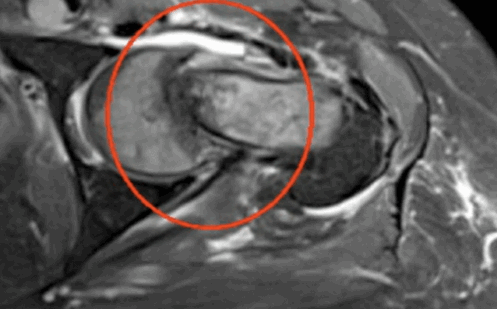

Импиджмент синдром на МР-фото

К механическому конфликту между бедренной головкой/шейкой и краем вертлужной впадины приводят одно- или двусторонние дефекты костей врожденного или приобретенного генеза. Видоизмененные компоненты сочленения вызывают дисфункцию конечности за счет соударения во время движения. Патологическое трение костей способствует разрастанию остеофитов на фоне постоянной травматизации вертлужной губы. Если своевременно не диагностировать заболевание и не начать лечение, последняя с течением времени разорвется., Хрящевая ткань сочленяющих костей будет разрушена. Подобный механический конфликт часто способствует формированию коксартроза и сопровождается прогрессирующим болевым синдромом.

МРТ тазобедренного сустава при феморо-ацетабулярном импинджмет-синдроме показывает возможные причины заболевания: